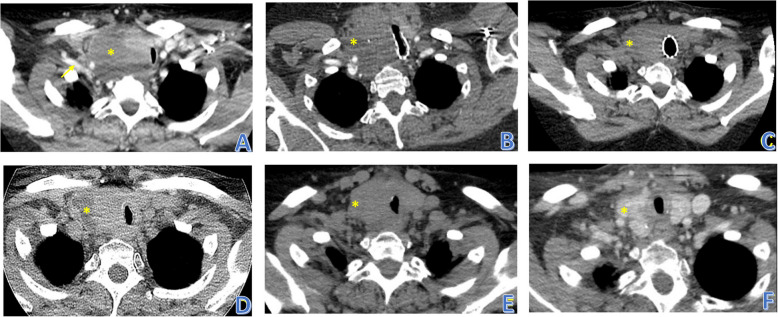

Results: A 63-year-old female presented with neck swelling and difficulty breathing. CT scan showed a large thyroid mass. Tracheal compression and deviation required stent placement and urgent radiation. Microscopic analysis showed neoplastic cells with frequent intracytoplasmic globules, including signet-ring cells. IHC stains were inconclusive to tumor type and metastasis from an occult primary was considered. However, PET-CT scan, mammography, and upper endoscopy were negative. Next-generation sequencing was performed revealing an ETV6-NTRK3 fusion favoring SC of the thyroid.